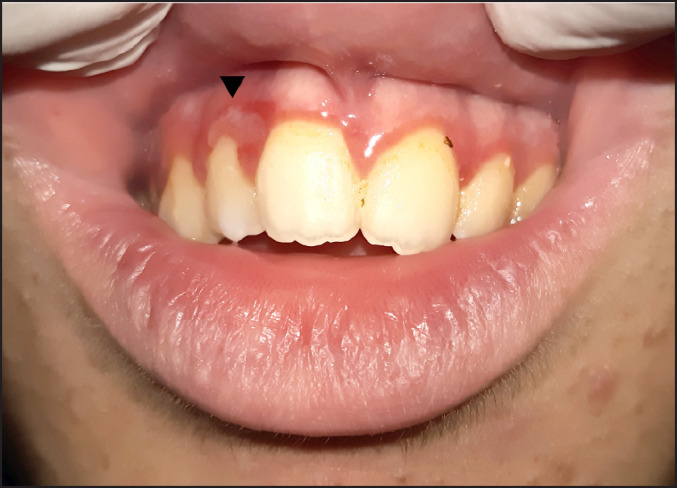

Methods: A 14-year-old boy with Asperger syndrome was referred for diagnosis and management of bright red granular overgrowths of the marginal gingiva and interdental papilla of the mandibular right incisors and marginal gingiva of the mandibular left incisor. A biopsy was performed on the interdental papilla between the mandibular right incisors.